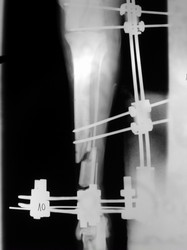

PRÁCTICAS CURSO DE FIJACIÓN EXTERNA PERFECCIONAMIENTO.

Híbrido.